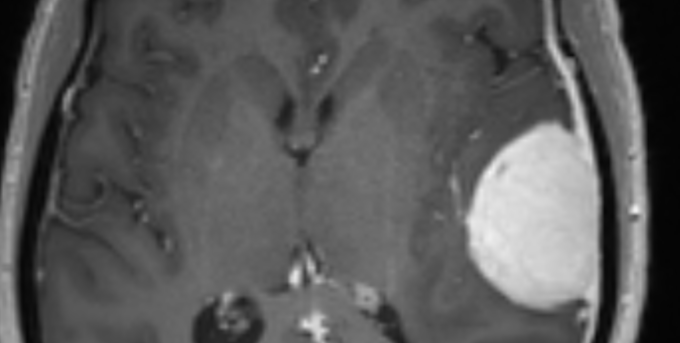

Meningiome Typique (Grade I)

- Bénin

- Masse extra-axiale Parasagittale ++

- Dural Tail

- Forte prise de contraste